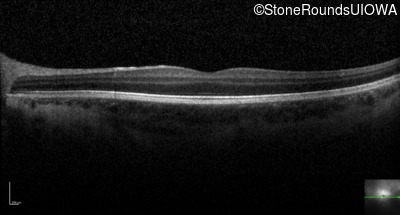

Optical Coherence Tomography - Left - 20/80 -2

Exemplar / OCT Stack

OCT Stack